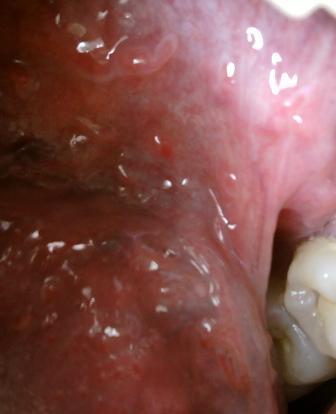

尿道口有绿豆大的小红疙瘩是怎么回事尖锐湿疣初期症状表现为淡红色的小丘疹。所以在的当发现尿道口有小红疙瘩的时候,应该及时去专业的医院进行必要的检查。确诊之后及时去医院进行治疗是很关键的。在患病之后根据自身病情,选择适合自己的治疗方法,才可以达到很好的治疗疾病的目的。长时间得不到及时有效地治疗,就会导致疾病加重,同时也失去了治疗的好时机,同时还会引发其他的并发症,比如,炎症,严重者还会导致不孕不育状况的发生,更严重的甚至是癌症。